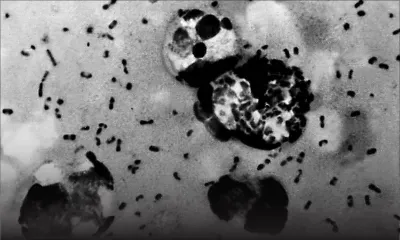

Coronavirus : le point sur la pandémie

Coronavirus: le point sur la pandémie